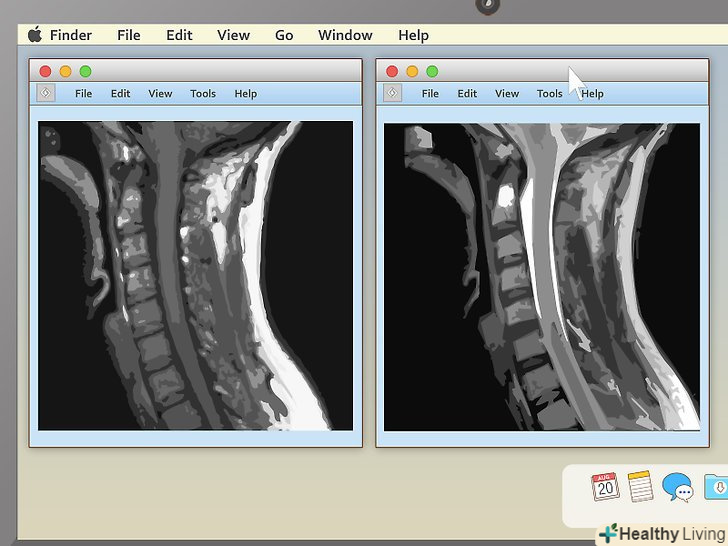

Виберіть відповідний режим перегляду.програми для перегляду МРТ часто вміють показувати більше одного зображення за раз. Завдяки цьому лікарям простіше порівнювати різні проекції однієї і тієї ж області або навіть знімки, зроблені в різний час. Непрофесіоналові краще вибрати режим, при якому буде показуватися тільки одне зображення за раз, і переглядати знімки послідовно. Проте, в програмі повинна бути кнопка, що дозволяє показувати 2, 4 і більше знімків одночасно, тому не бійтеся її натискати.

Вивчіть структуру хребців, якщо ви розглядаєте МРТ хребта.МРТ хребта прочитати чи не найпростіше іншого (особливо в саггитальной проекції). Пошукайте порушення в розташуванні хребців або міжхребцевих дисків. Якщо хоча б один буде не не своєму місці (як в прикладі вище), це може стати джерелом сильного болю.- За хребтом у саггітальній проекції ви побачите щось біле, схоже на мотузку. Це спинний мозок, який пов'язаний з усіма нервовими закінченнями в організмі. Пошукайте ділянки, де хребці або диски притискають спинний мозок. Оскільки нервові закінчення дуже чутливі, навіть невеликий тиск призводить до болю.